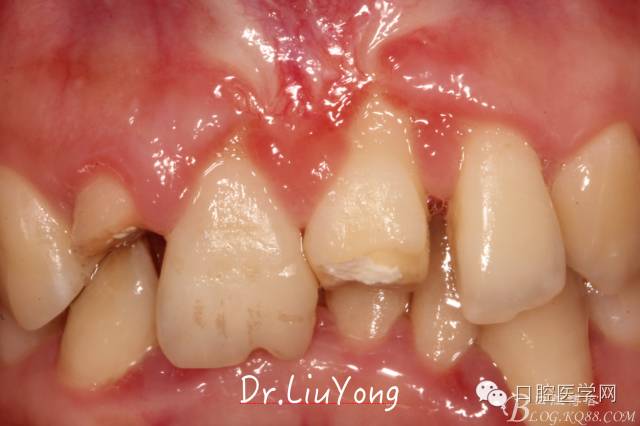

骨塊固定兩周后復(fù)查,如上圖:

在松動(dòng)牙固定的同時(shí),嘗試保留B1唇側(cè)折裂牙槽骨塊,拆除縫線后,局部沖洗,牙周塞治劑覆蓋并固定游離骨塊。囑患者加強(qiáng)口腔衛(wèi)生,氯己定漱口液含漱,兩周后復(fù)查。兩周后拆除塞治劑,骨塊仍為游離活動(dòng)狀態(tài),去除游離骨塊,局部沖洗上藥。